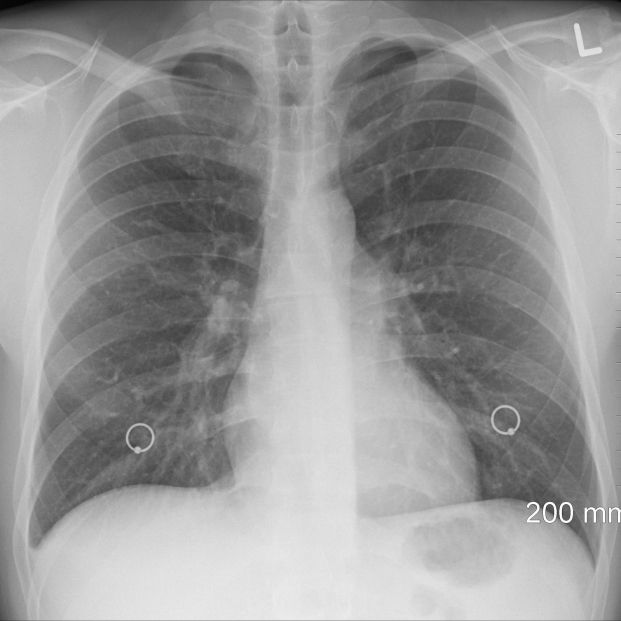

Lógicamente, el propio envejecimiento natural hace que una persona mayor tenga menos defensas frente al humo y las sustancias tóxicas del tabaco. Además, hay que tener en cuenta que alguien que fuma superados los 50, lo más probable es que sea porque adquirió el hábito tiempo atrás, por lo que, las malas consecuencias de los cigarrillos acumulados pueden agravar cualquier enfermedad, con especial incidencia en aquellas que tienen relación con el sistema respiratorio.

Riesgo de neumonía

Son muchas las razones que indican que el tabaco es aún peor a medida que se van cumpliendo años. La Sociedad Española de Neumología y Cirugía Torácica afirma que el tabaquismo activo y pasivo es un factor de riesgo para desarrollar neumonía sobre todo a partir de los 60 años. Además, a medida que el sistema respiratorio se debilita, la posibilidad de padecer Enfermedad Pulmonar Obstructiva Crónica (EPOC), aumenta. En este sentido, la citada Sociedad recuerda que el 80% de los pacientes de EPOC han sido fumadores.